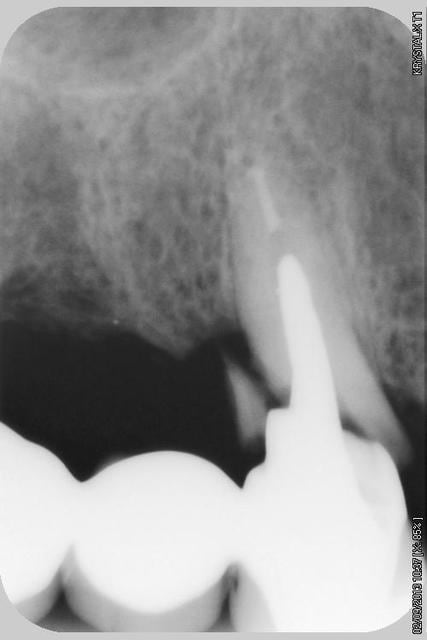

13 fenestration vestibulaire j'utilise la paroi palatine, lame N°15, spreader, expansion et pose d'un 40140

Puis 40120 en 15 avec léger SL, à l'ostéotome, et 40120 en 17.

Le pano est d'avant les extractions